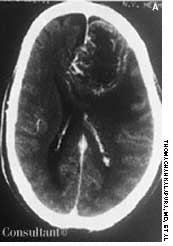

A 57-year-old man complained of a severe headache of sudden onset while he was lifting heavy boxes. Within minutes, he collapsed and became unconscious. On arrival at the emergency department, the patient was deeply comatose. His pupils were 7 mm, fixed, and unreactive to light; brainstem reflexes were absent, and he was unresponsive to noxious stimulation. His blood pressure was 210/120 mm Hg; he had no known history of hypertension.